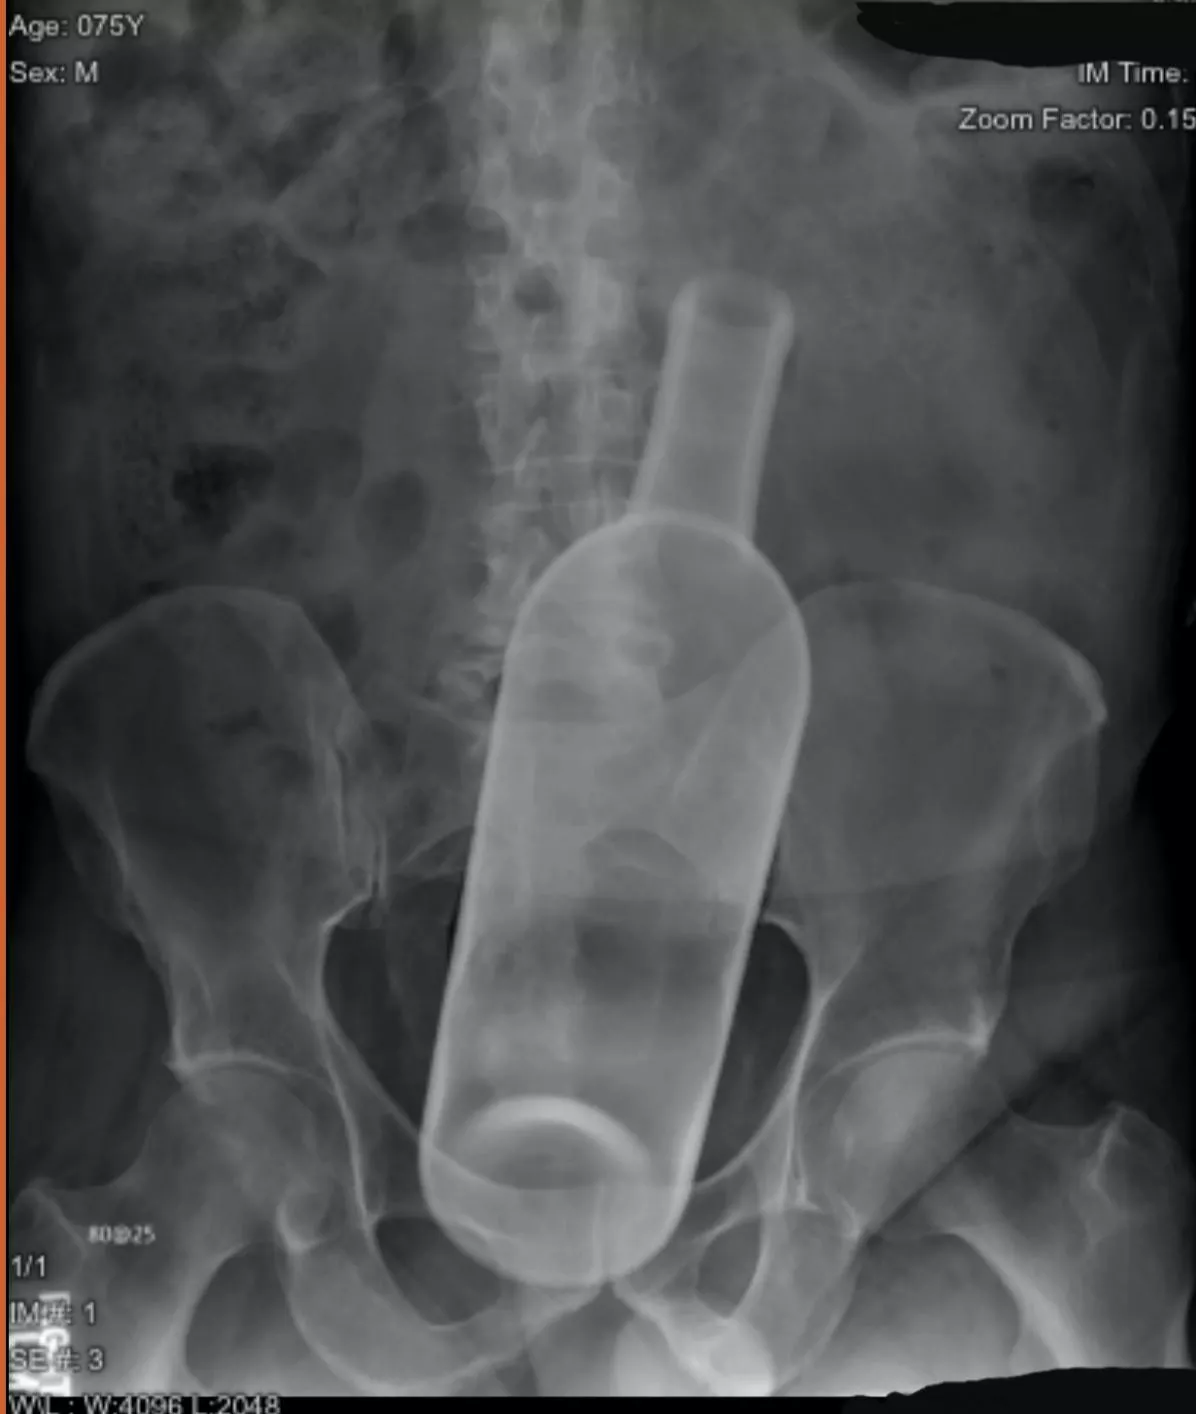

In response to the other post involving a wine bottle and Cindy rose